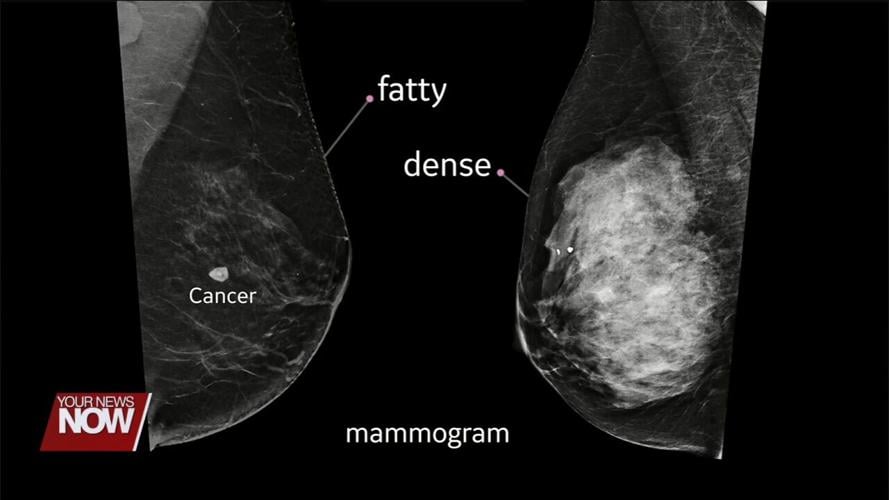

"The fibroglandular tissue is white on a mammogram, and all breast cancers are white on a mammogram, so if you have a lot of this white, dense glandular tissue, a little teeny tiny cancer could be easily missed or obscured. So when we do that automated breast ultrasound tool that we have, that other imaging modality, all cancers on that modality are gray or a certain shade of gray, so when we have that white cancer, it's very easily seen because it shows up gray on the ultrasound, so we're able to see through all that white glandular tissue in the ultrasound, so those cancers just pop right out. They're very easily seen," added Dr. Weyer.